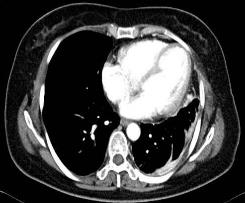

胸部CT检查提示:左肺癌术后,纵隔向左移位,左肺体积缩小,其内见多发斑片索条影,左侧胸膜增厚,前胸壁见大小约3.0x3.6cm团块状影,边缘不 整,部分肋骨及心包受侵。左前胸壁考虑:转移瘤可能。